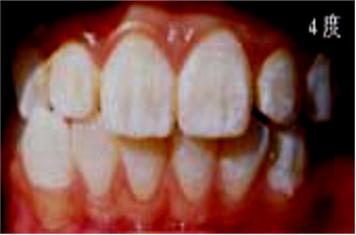

儿童牙齿发育过程中摄入过量的氟会引起氟斑牙:

中度:上中切齿或全口牙整个牙面出现白垩,失去光泽,有明显着色。有的出现小点状凹坑。

重度:全口牙面呈白垩,出现散在坑凹状缺损或融合成片状缺损,有较重的着色。